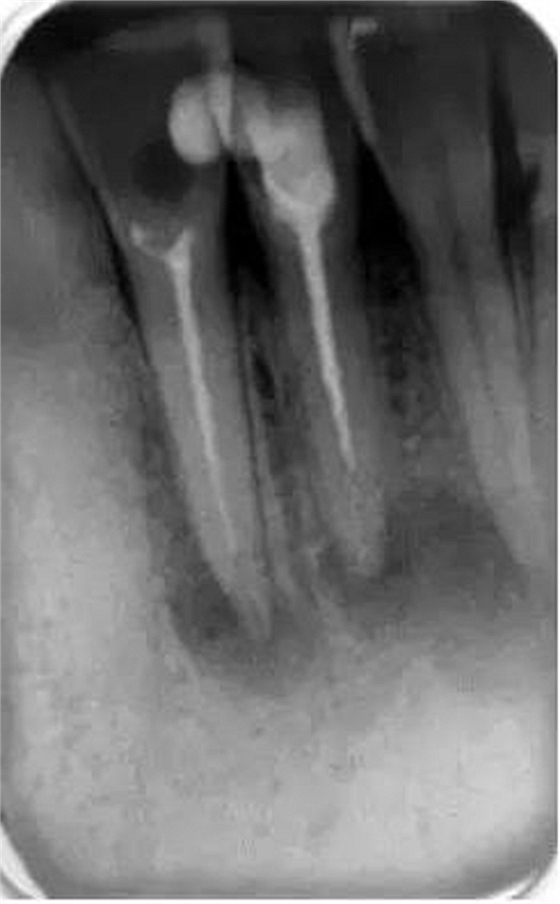

它還有助于臨床醫(yī)生決定他是否有能力進行該病例的治療還是應(yīng)該將患者轉(zhuǎn)診到??漆t(yī)生處進行治療。還可以在治療前明確髓腔內(nèi)是否有髓石以及牙齒或根管內(nèi)是否有其他阻塞物(如樁、釘、分離的儀器或根填充材料)(圖2)。這是很重要的,因為它會給臨床醫(yī)生一些預(yù)后和治療中可能出現(xiàn)的一些問題的提示。所有這些因素必須在治療前與患者進行溝通,以便其決定是否要繼續(xù)進行根管治療。